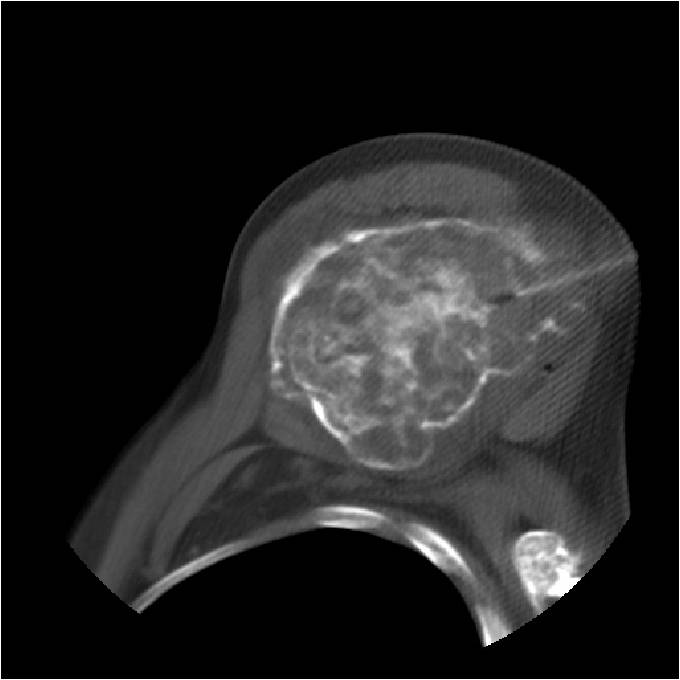

- Localized, radiolucent defect usually with punctate calcifications

- Calcifications are typical but not always present

- Matrix may demonstrate various degrees of calcification

- Calcifications are stippled, punctate, popcorn like calcifications and “Ring and Arc” calcifications

- Cartilage tumors grow in a lobular manner. The perimeters of the lobules undergo

- enchondral ossification that may calcify. If the entire perimeter of the lobule calcifies it appears

- radiographically as a “Ring”. If a portion of the perimeter of a lobule calcifies it forms an “Arc” on

- an X-ray.

- Chondroid matrix with calcifications in majority of tumors

- Approximately 20% have limited or no calcifications

- Endosteal erosion>2/3 cortical thickness on a CT scan